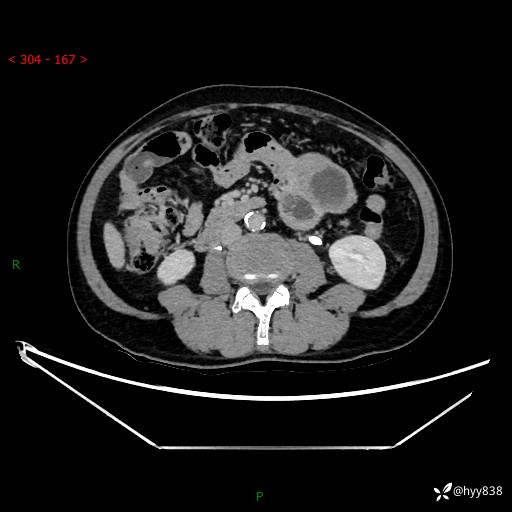

年龄:61岁

主诉:发现腹膜后肿瘤3天

腹部CT平扫+增强(动脉期+静脉期)